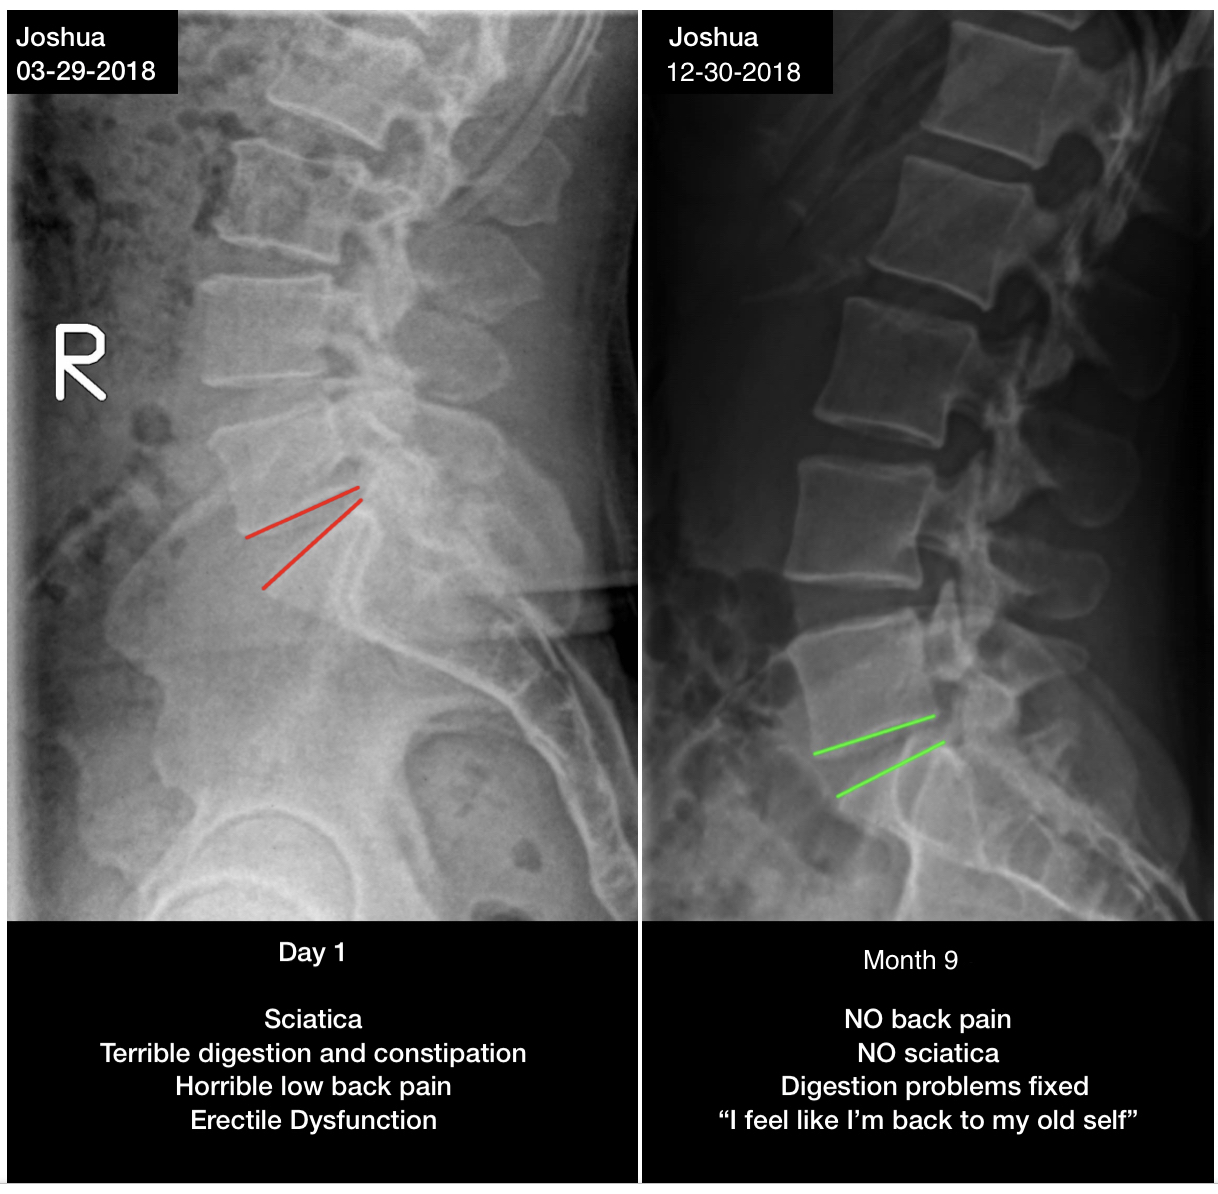

Sciatica, low back pain, digestion issues, and erectile dysfunction resolved in 9 months. "I feel like I'm back to my old self."